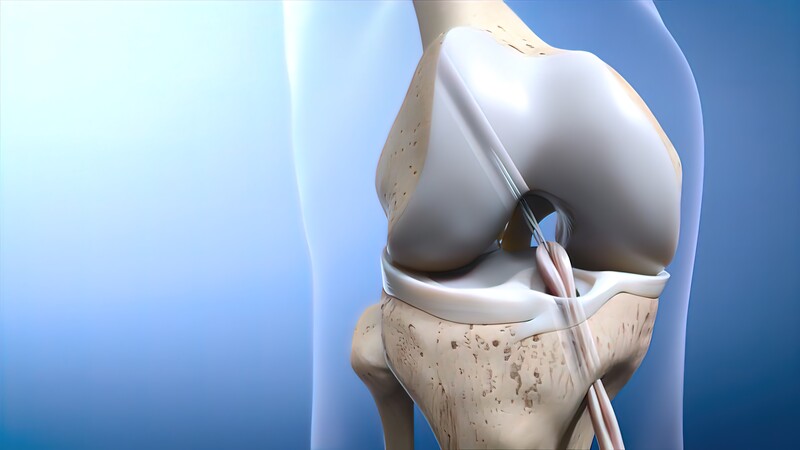

If the ACL is completely torn, surgical intervention may be required to restore knee function. ACL reconstruction surgery is the most common procedure, and it typically involves replacing the damaged ligament with a tissue graft.

- ACL Reconstruction Surgery: During surgery, a graft from either the patient’s own tissue (autograft), a donor (allograft), or synthetic material is used to replace the torn ACL. The surgery is typically performed arthroscopically, meaning it’s minimally invasive, leading to faster recovery times.